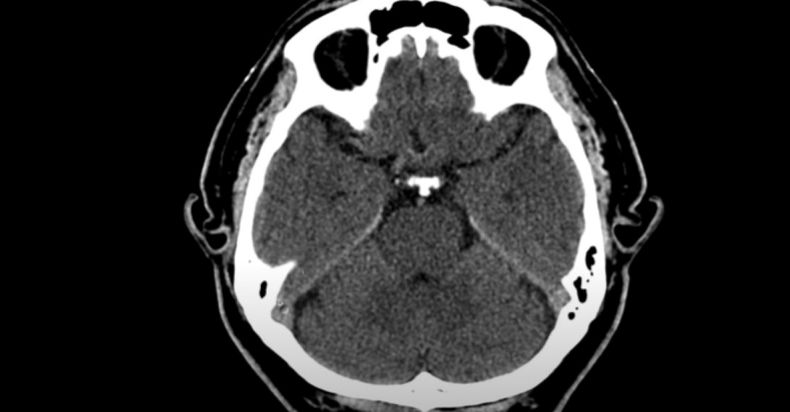

Crean un tumor cerebral activo en 3D que ayudará a investigar patologías vinculadas a este órgano

Apelando a una impresión 3D, investigadores de la Universidad de Tel Aviv crearon un gliobastoma activo, uno de tumores cerebrales más letales, que ayudará a avanzar en la detección de tratamientos y el desarrollo de medicamentos.